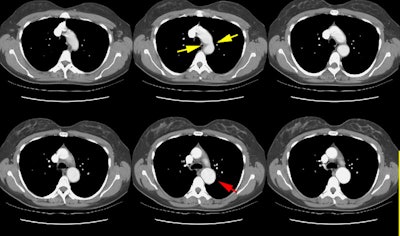

The CT scan demonstrated a focal aortic narrowing just beyond the ligamentum arteriosus (yellow arrows) with post-stenotic dilatation of the descending aorta (red arrow). An angiogram confirmed the CT findings and demonstrated a significant pressure gradient across the coarctation.